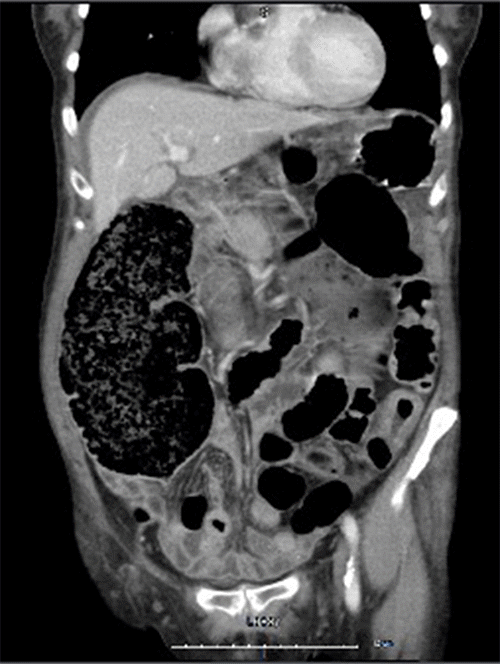

An 83-year-old female with no prior abdominal surgery was evaluated in the emergency room due to approximately 24 hours of acute onset abdominal pain and distention. She denied bright red blood per rectum but ascribed to decreased flatus and decreased stool output. Initial clinical examination demonstrated a mildly tender, distended abdomen with no associated peritonitis, rigidity, or guarding. Her most recent colonoscopy was ten years prior, at which time multiple polyps were identified but no large tumor. Abdominal computer tomography (CT) scan with intravenous contrast revealed the presence of large bowel to large bowel intussusception in the descending colon. The intussuscepted segment was approximately 8.5 cm in length (Figure 1).

Figure 1. CT Abdomen Showing Intussuscepted Segment Approximately 8.5 cm in Length. Published with Permission